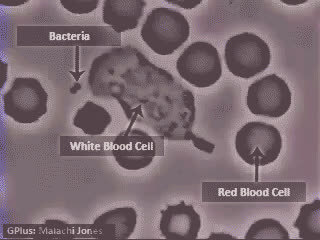

9.白细胞: 当病菌侵入人体体内时,白细胞能通过变形而穿过毛细血管壁,集中到病菌入侵部位。这就像在穿越时空隧道。

3.这是中性粒细胞追击金黄色葡萄球菌的一个过程。免疫细胞捕捉细菌时是不是超萌!